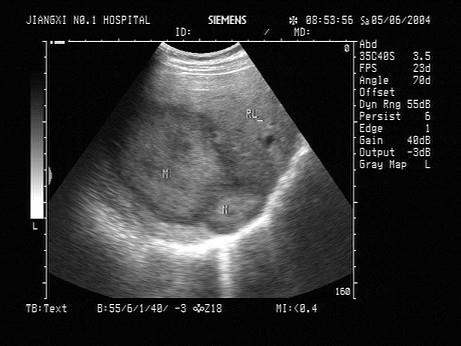

问题 男,49岁,上腹不适1个月余。结合超声声像图,诊断为?(?)

选项 A.肝血管瘤 B.肝癌 C.局限性脂肪肝 D.肝脓肿 E.肝囊肿

答案 B